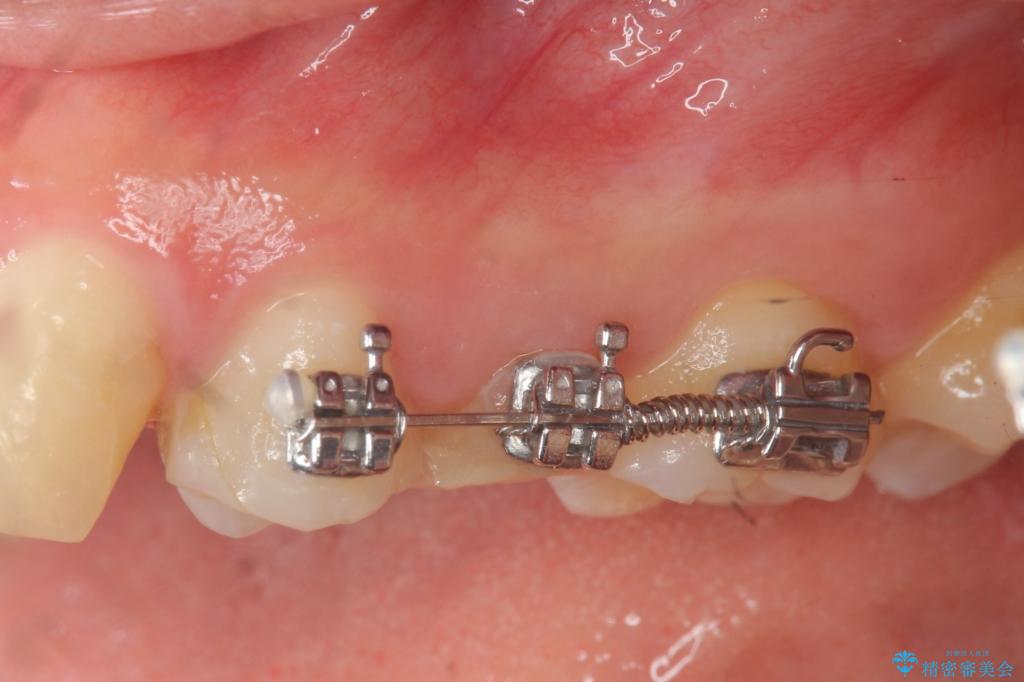

- 部分ワイヤー矯正

虫歯が大きかったことから、神経の温存はできたものの歯ぐきよりも深い虫歯の問題を解決するため部分矯正治療を併用したセラミック治療を行うこととしました。

当初、歯ぐきよりも深い虫歯のぞんざいや、歯のポジションに問題がありましたがマルチブラケットを用いた部分矯正を行うことで適切な位置へと歯を移動させ、歯周環境を整えたセラミック治療を行うことができました。